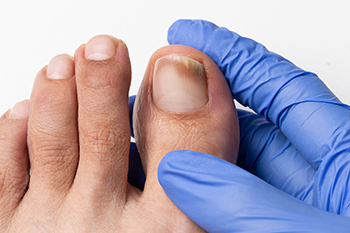

Diabetes can lead to various foot and toenail issues due to poor circulation, nerve damage, and compromised immune function. Common toenail problems in diabetics include onycholysis, which is a separation of the nail from the nail bed, ingrown toenails, fungal infections, and periungual erythema, which is redness around the nail. These conditions often arise because diabetes weakens the body’s ability to fight infections and heal wounds. Symptoms include pain, swelling, discoloration, or a thickened nail, which may become brittle or discolored. Fungal infections may cause the nail to crumble or thicken, while ingrown toenails can cause tenderness and redness. Treatment may involve antifungal medications, proper nail trimming techniques, or the use of custom orthotics to alleviate pressure. In more severe cases, a podiatrist may recommend medical intervention or even nail removal. Proper foot care, including regular check-ups with a podiatrist, is essential for preventing complications. If you are dealing with these types of issues, it is suggested that you make an appointment with a podiatrist.

If left untreated, toenail fungus may spread to other toenails, skin, or even fingernails. If you suspect you have toenail fungus it is important to seek treatment right away. For more information about treatment, contact Manisha Mehta, DPM of Detroit, MI. Our doctor can provide the care you need to keep you pain-free and on your feet.